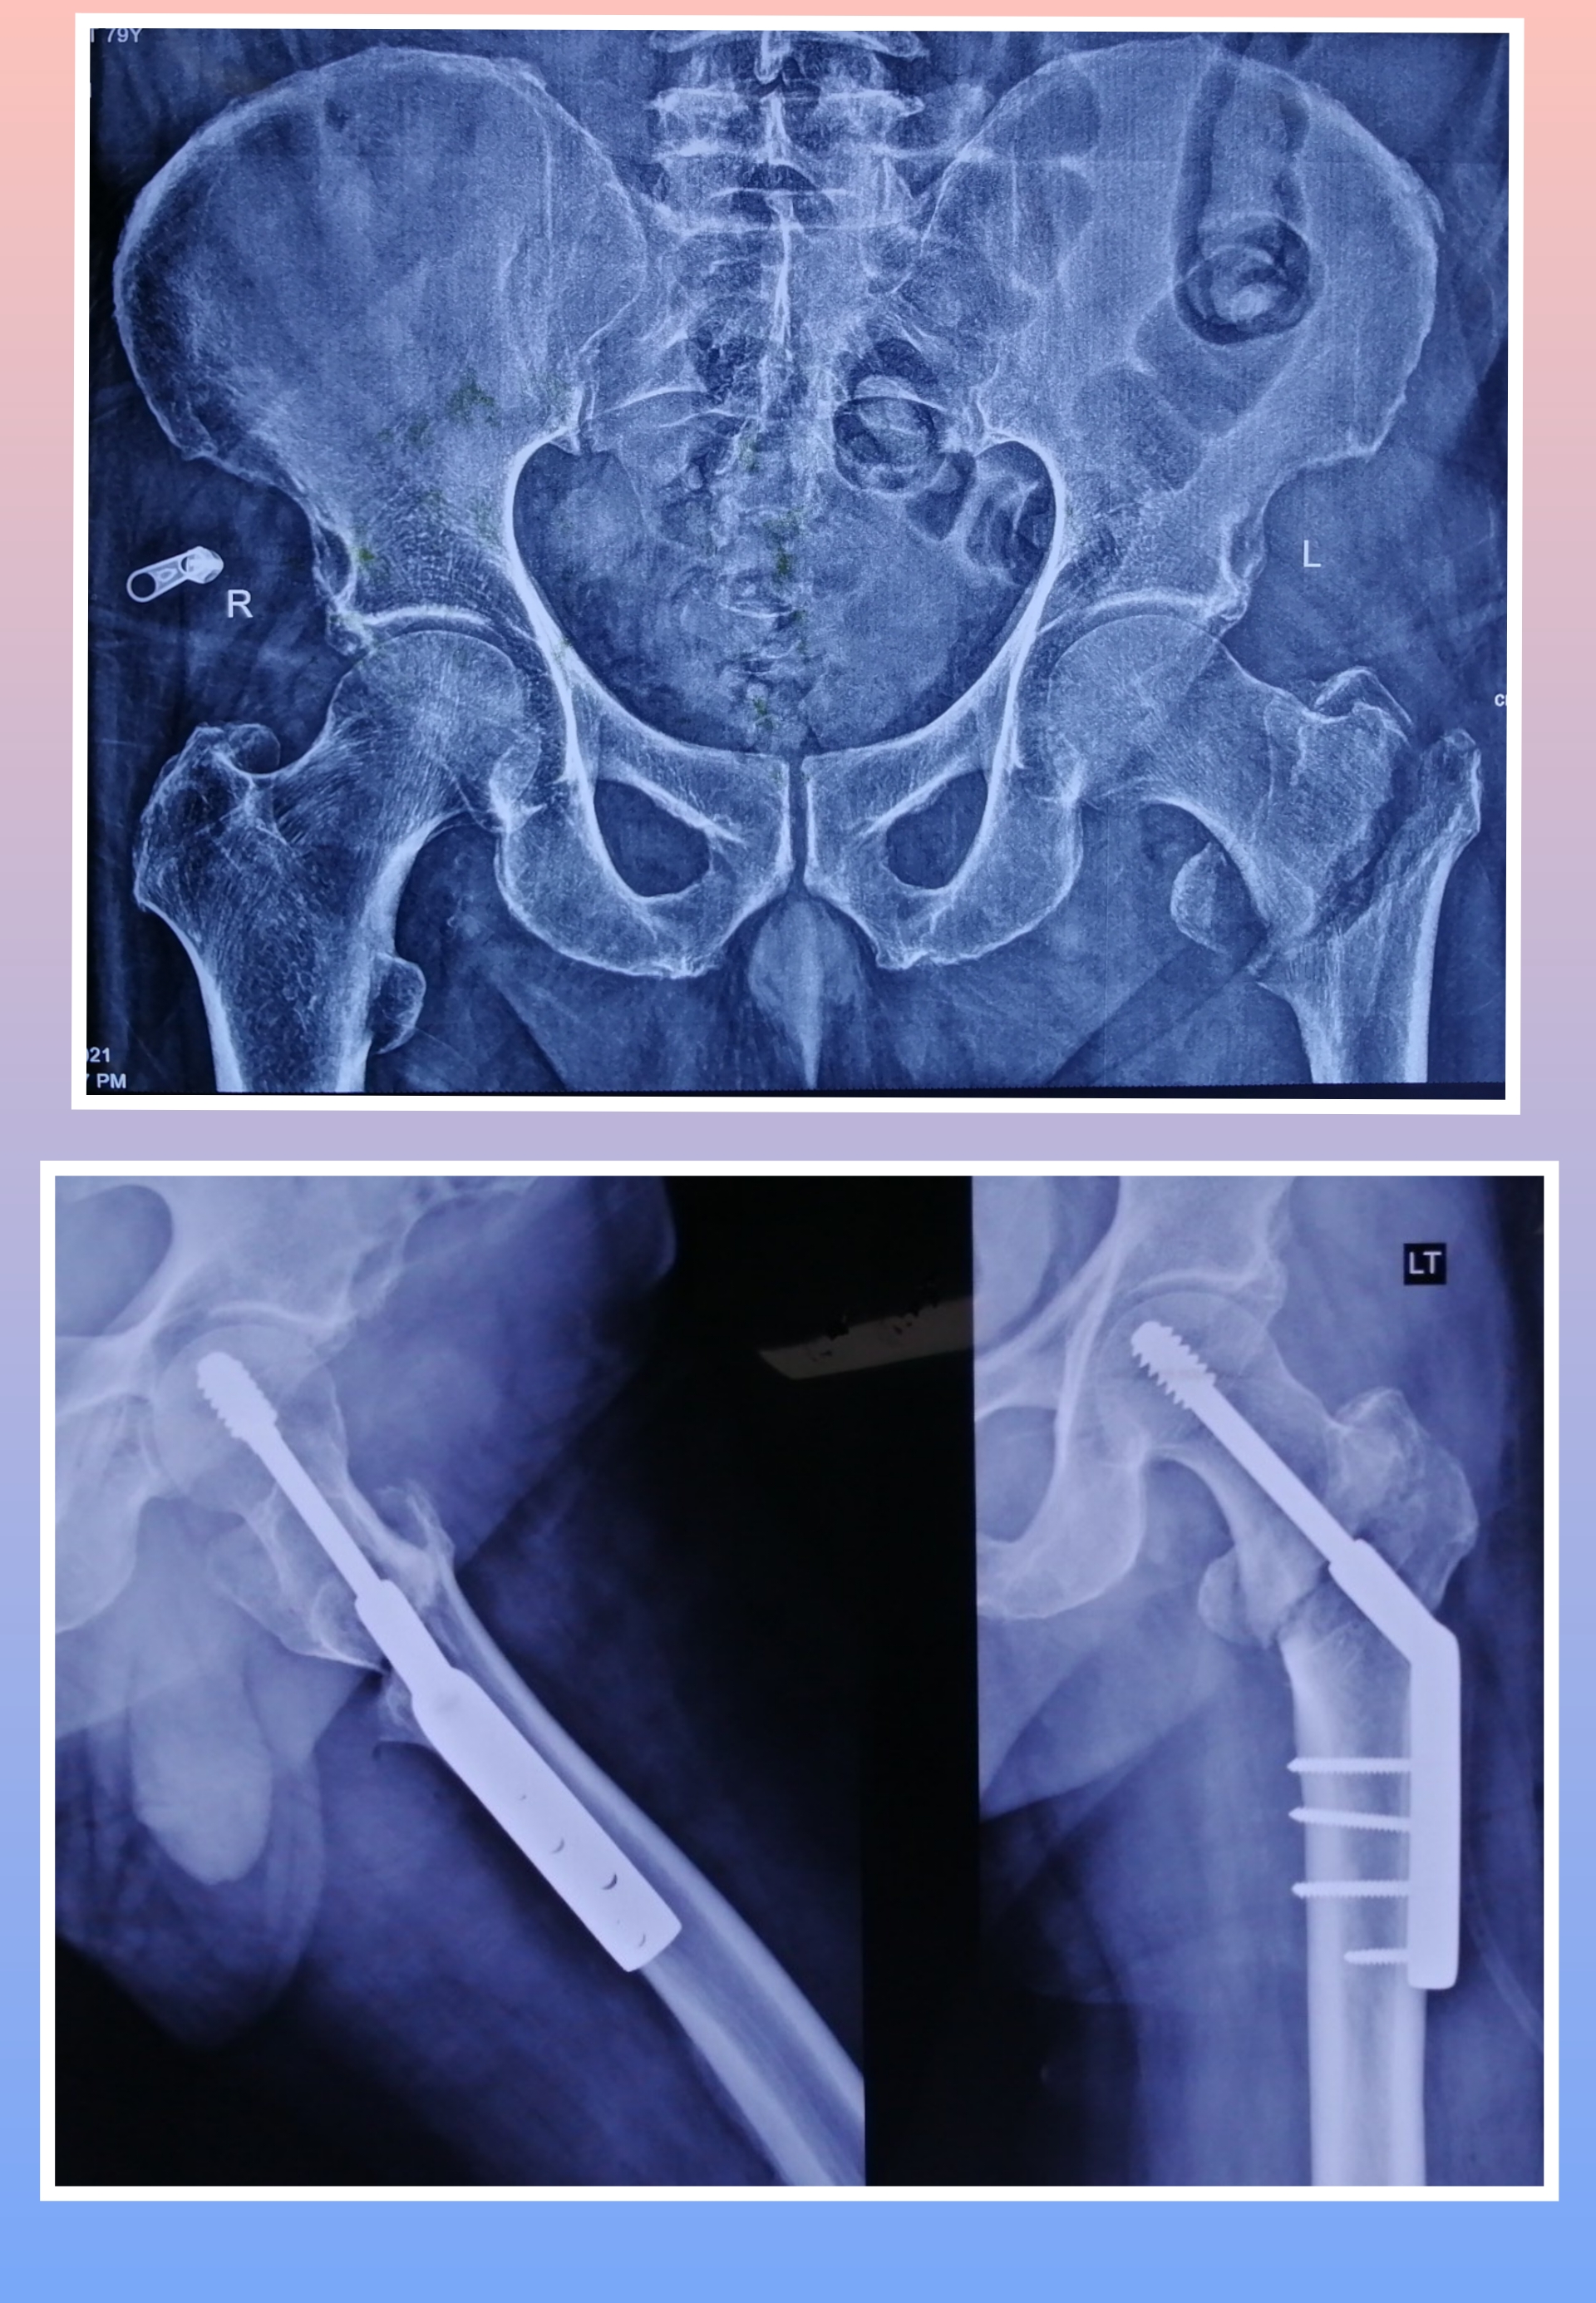

Warning: Graphic Content

The following section contains graphic images of surgical procedures. These images are intended for educational purposes and may be disturbing to some viewers. Viewer discretion is advised.

Surgeries